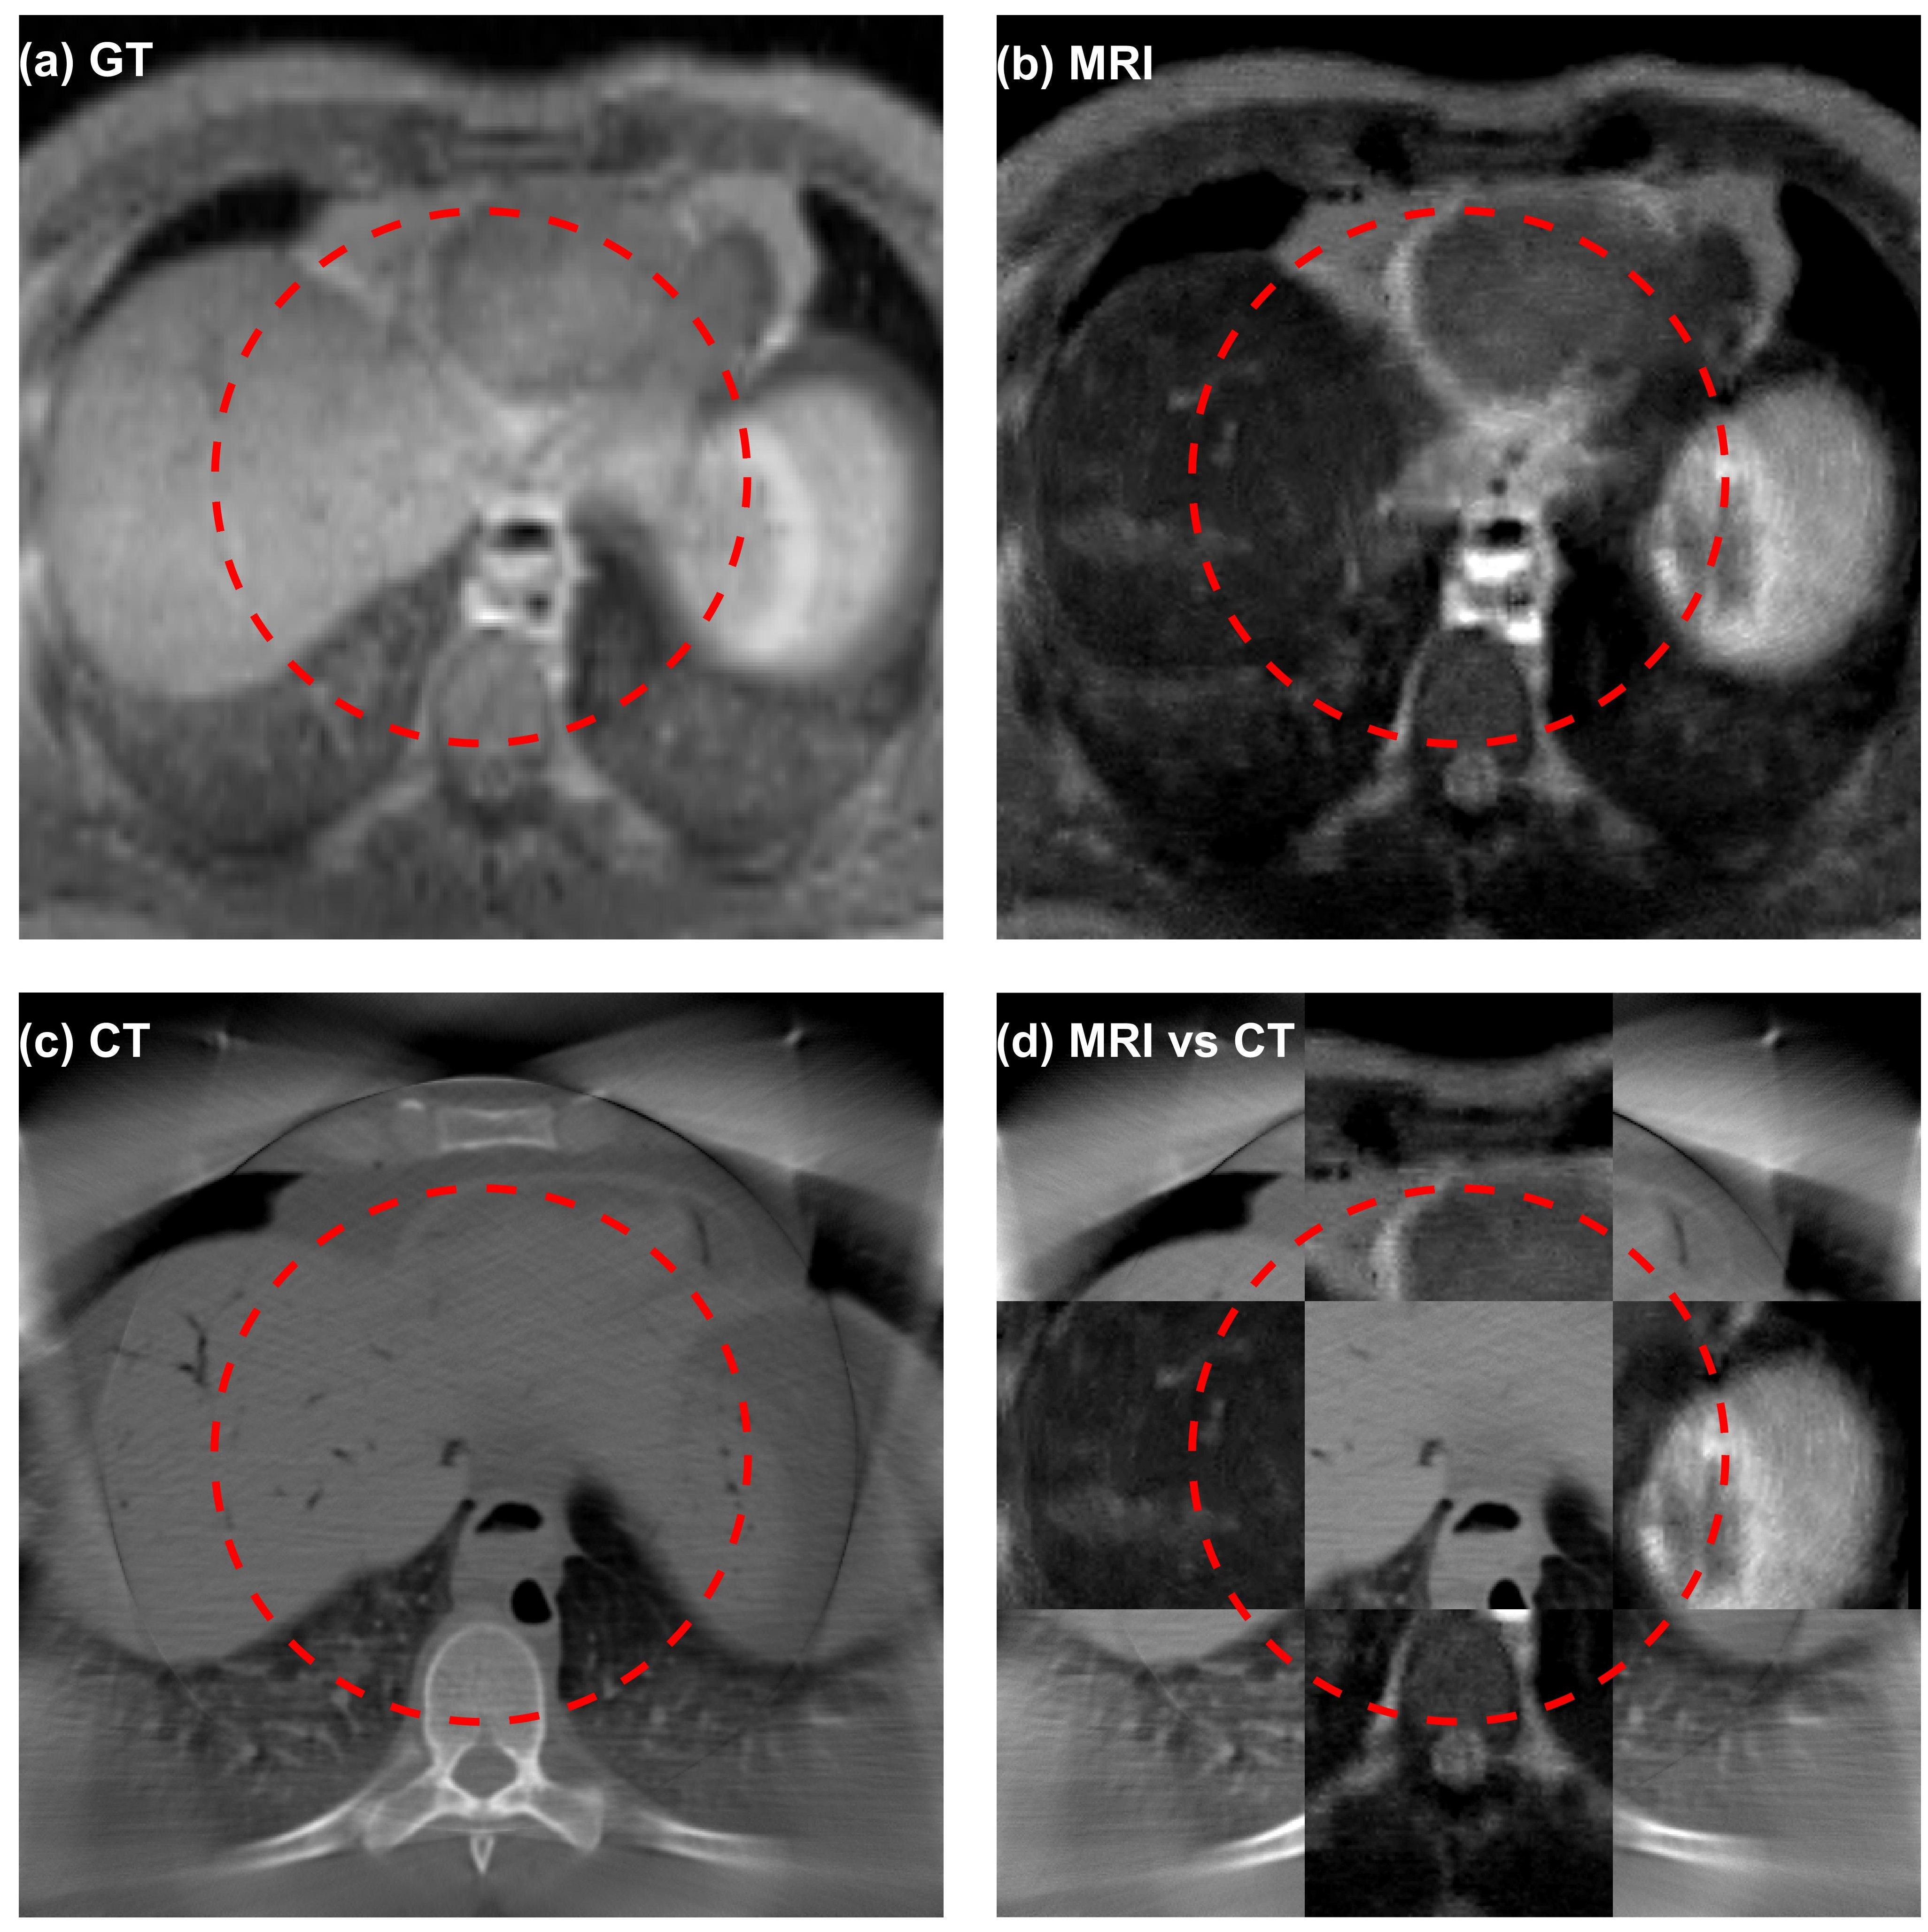

We present in Figures 7 and 8 the results from the neck and chest sites. In each figure, in addition to presenting the simulation results of the CT and MR images, we also generated a blended view by displaying CT and MRI images in different squares. The capability of integrated CT-MRI imaging in the same spatial coordinate system is expected to offer advantages in a variety of clinical tasks, such as disease diagnosis and therapy planning.

Figure 7: Axial planes of (a) proton density image of the VHP neck phantom, (b) simulated MR image (TR=1,000 ms,TE=80 ms, and NEX=16), (c) simulated CT image, and (d) blended view of MRI and CT images. The dashed red circles indicate the targeted FOV of 15 cm in diameter.

Figure 8: Axial planes of (a) proton density image of the VHP chest phantom, (b) simulated MR image (TR=1,000 ms,TE=80 ms, and NEX=16), (c) simulated CT image, and (d) blended view of MRI and CT images. The dashed red circles indicate the targeted FOV of 15 cm in diameter.